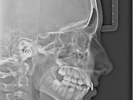

Teleradiografie / Cephalometric X-Ray

Teleradiografie / Cephalometric X-Ray – ..